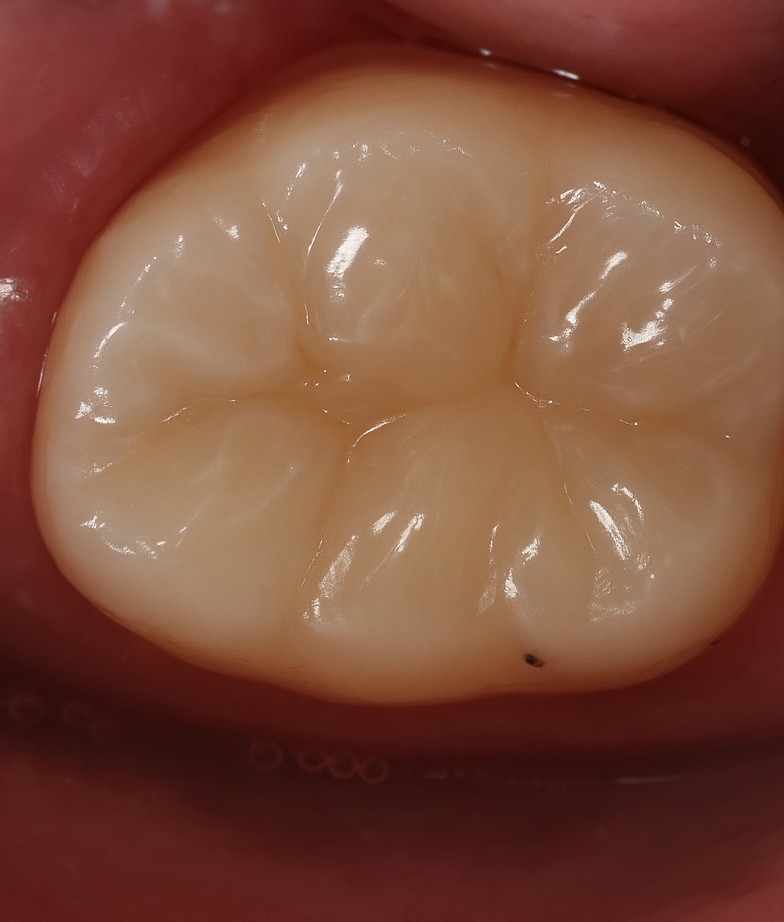

1. Initial Presentation

The patient presented with a deep occlusal-proximal carious lesion and discoloration (Fig 1). The tooth was sensitive to cold and percussion, confirming irreversible pulpitis on vitality testing. Radiographic assessment revealed pulpal involvement but sufficient ferrule for adhesive restoration.